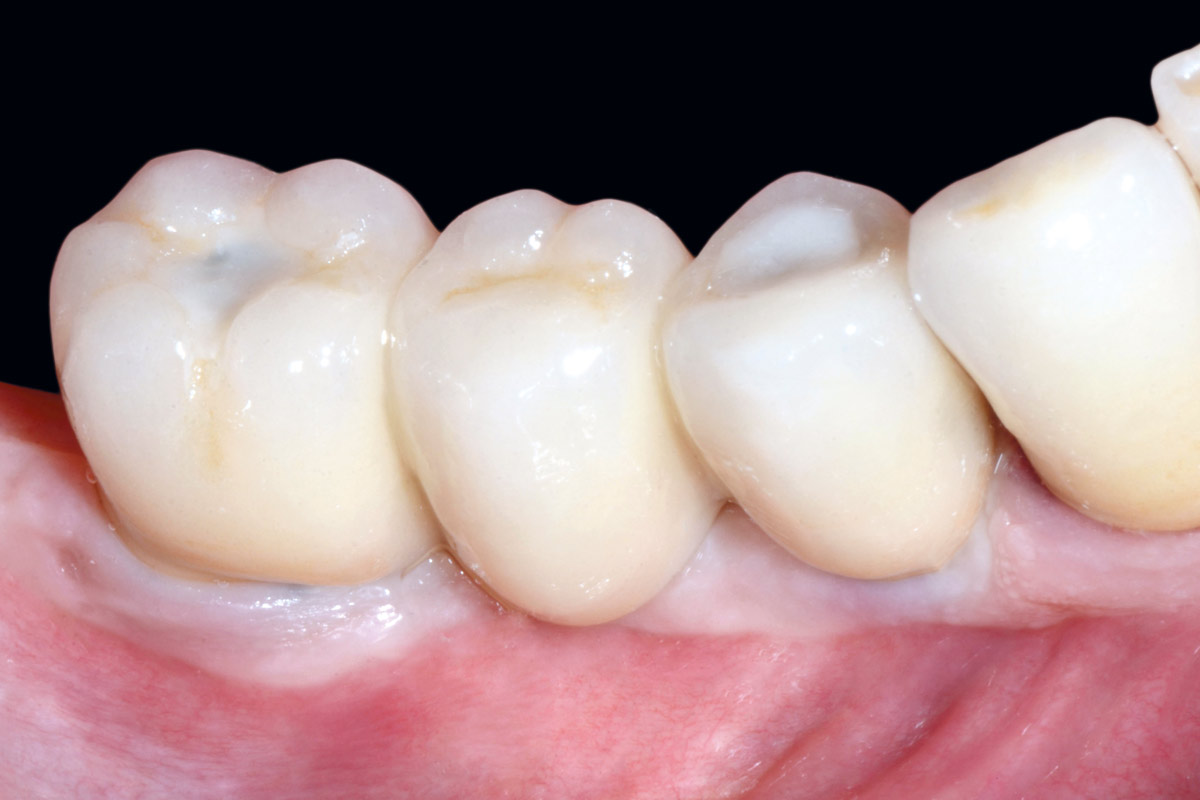

Multiple socket preservation in the mandibular with collacone® max – Dr. D. Jelušić